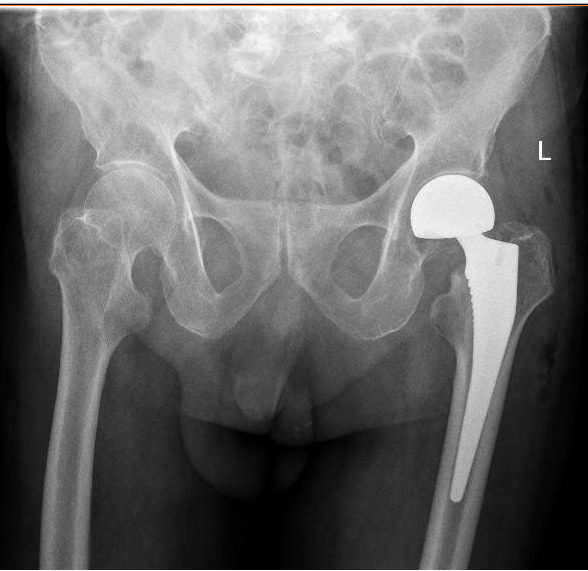

“王大爷入院时,检查发现左侧股骨颈骨折,也就是我们常说的‘髋关节骨折’。老人发生髋关节骨折,也被称为‘人生最后一次骨折’,死亡率近60%。让人痛心的是很多老人是死于骨折后长期卧床导致的并发症。”市中医医院骨科主治医师吴东海介绍,老人发生骨折后,如果采用保守治疗,长期卧床容易发生压力性损伤、尿路感染、肺部感染等并发症,生活质量几乎无从谈起,更有可能因并发症威胁到生命。比较好的解决方案是尽快进行手术,让老人重新站起来,减少并发症的发生,提高生活质量,也减轻家人的负担。

“通过团队的默契配合,王大爷的手术我们仅用30多分钟就顺利完成,术中出血量不到50ML,做到了手术时间少,出血少,把各种风险降低到最小化。手术后,配合术后护理、内科治疗、中医手法康复等,让老人获得了快速康复。”吴东海说,随着技术的进步,越来越多的高龄患者得益于先进的综合治疗方法,这将让更多的高龄患者提高生活质量,重新焕发新活力。

骨伤三科重点专业技术:髋、膝骨关节外科、运动医学关节镜技术等关节伤病的治疗。以收治髋膝关节疾病和运动医学(关节镜)损伤治疗为主的特色科室。主要是对髋、膝关节疾病如先天性髋关节复位、髋关节发育不良、股骨颈骨折、股骨头坏死、股骨粗隆骨折、膝关节周围骨折、髋膝关节炎、膝关节半月板、交叉韧带损伤、肩踝运动损伤疾病等综合治疗,采用现代先进理念和技术进行股骨头坏死早期控制、髋、膝关节置换、骨折的内外固定等治疗手段,帮助患者最快恢复健康。关节镜专科治疗各种关节疾病,如关节半月板损伤、膝关节叉韧带断裂,肩周炎、肩袖损伤、踝关节滑膜炎、关节游离体取出、关节软骨损伤修复重建等。